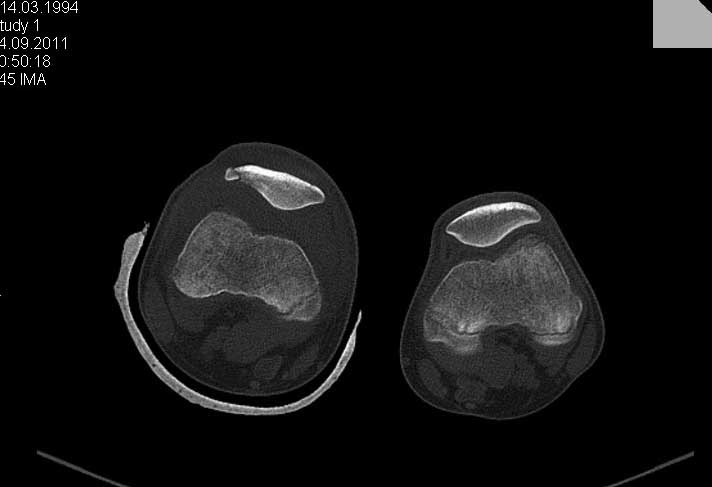

Обратился ребёнок 15 лет с оскольчатым переломом надколенника. Давность травмы 1

неделя.Поделитеся пожалуйста опытом. 1. Надо ли оперировать? 2. Не ухудшит ли

спице-проволочный шов стояние отломков. 3. Может не оставить так и лечить консервативно?